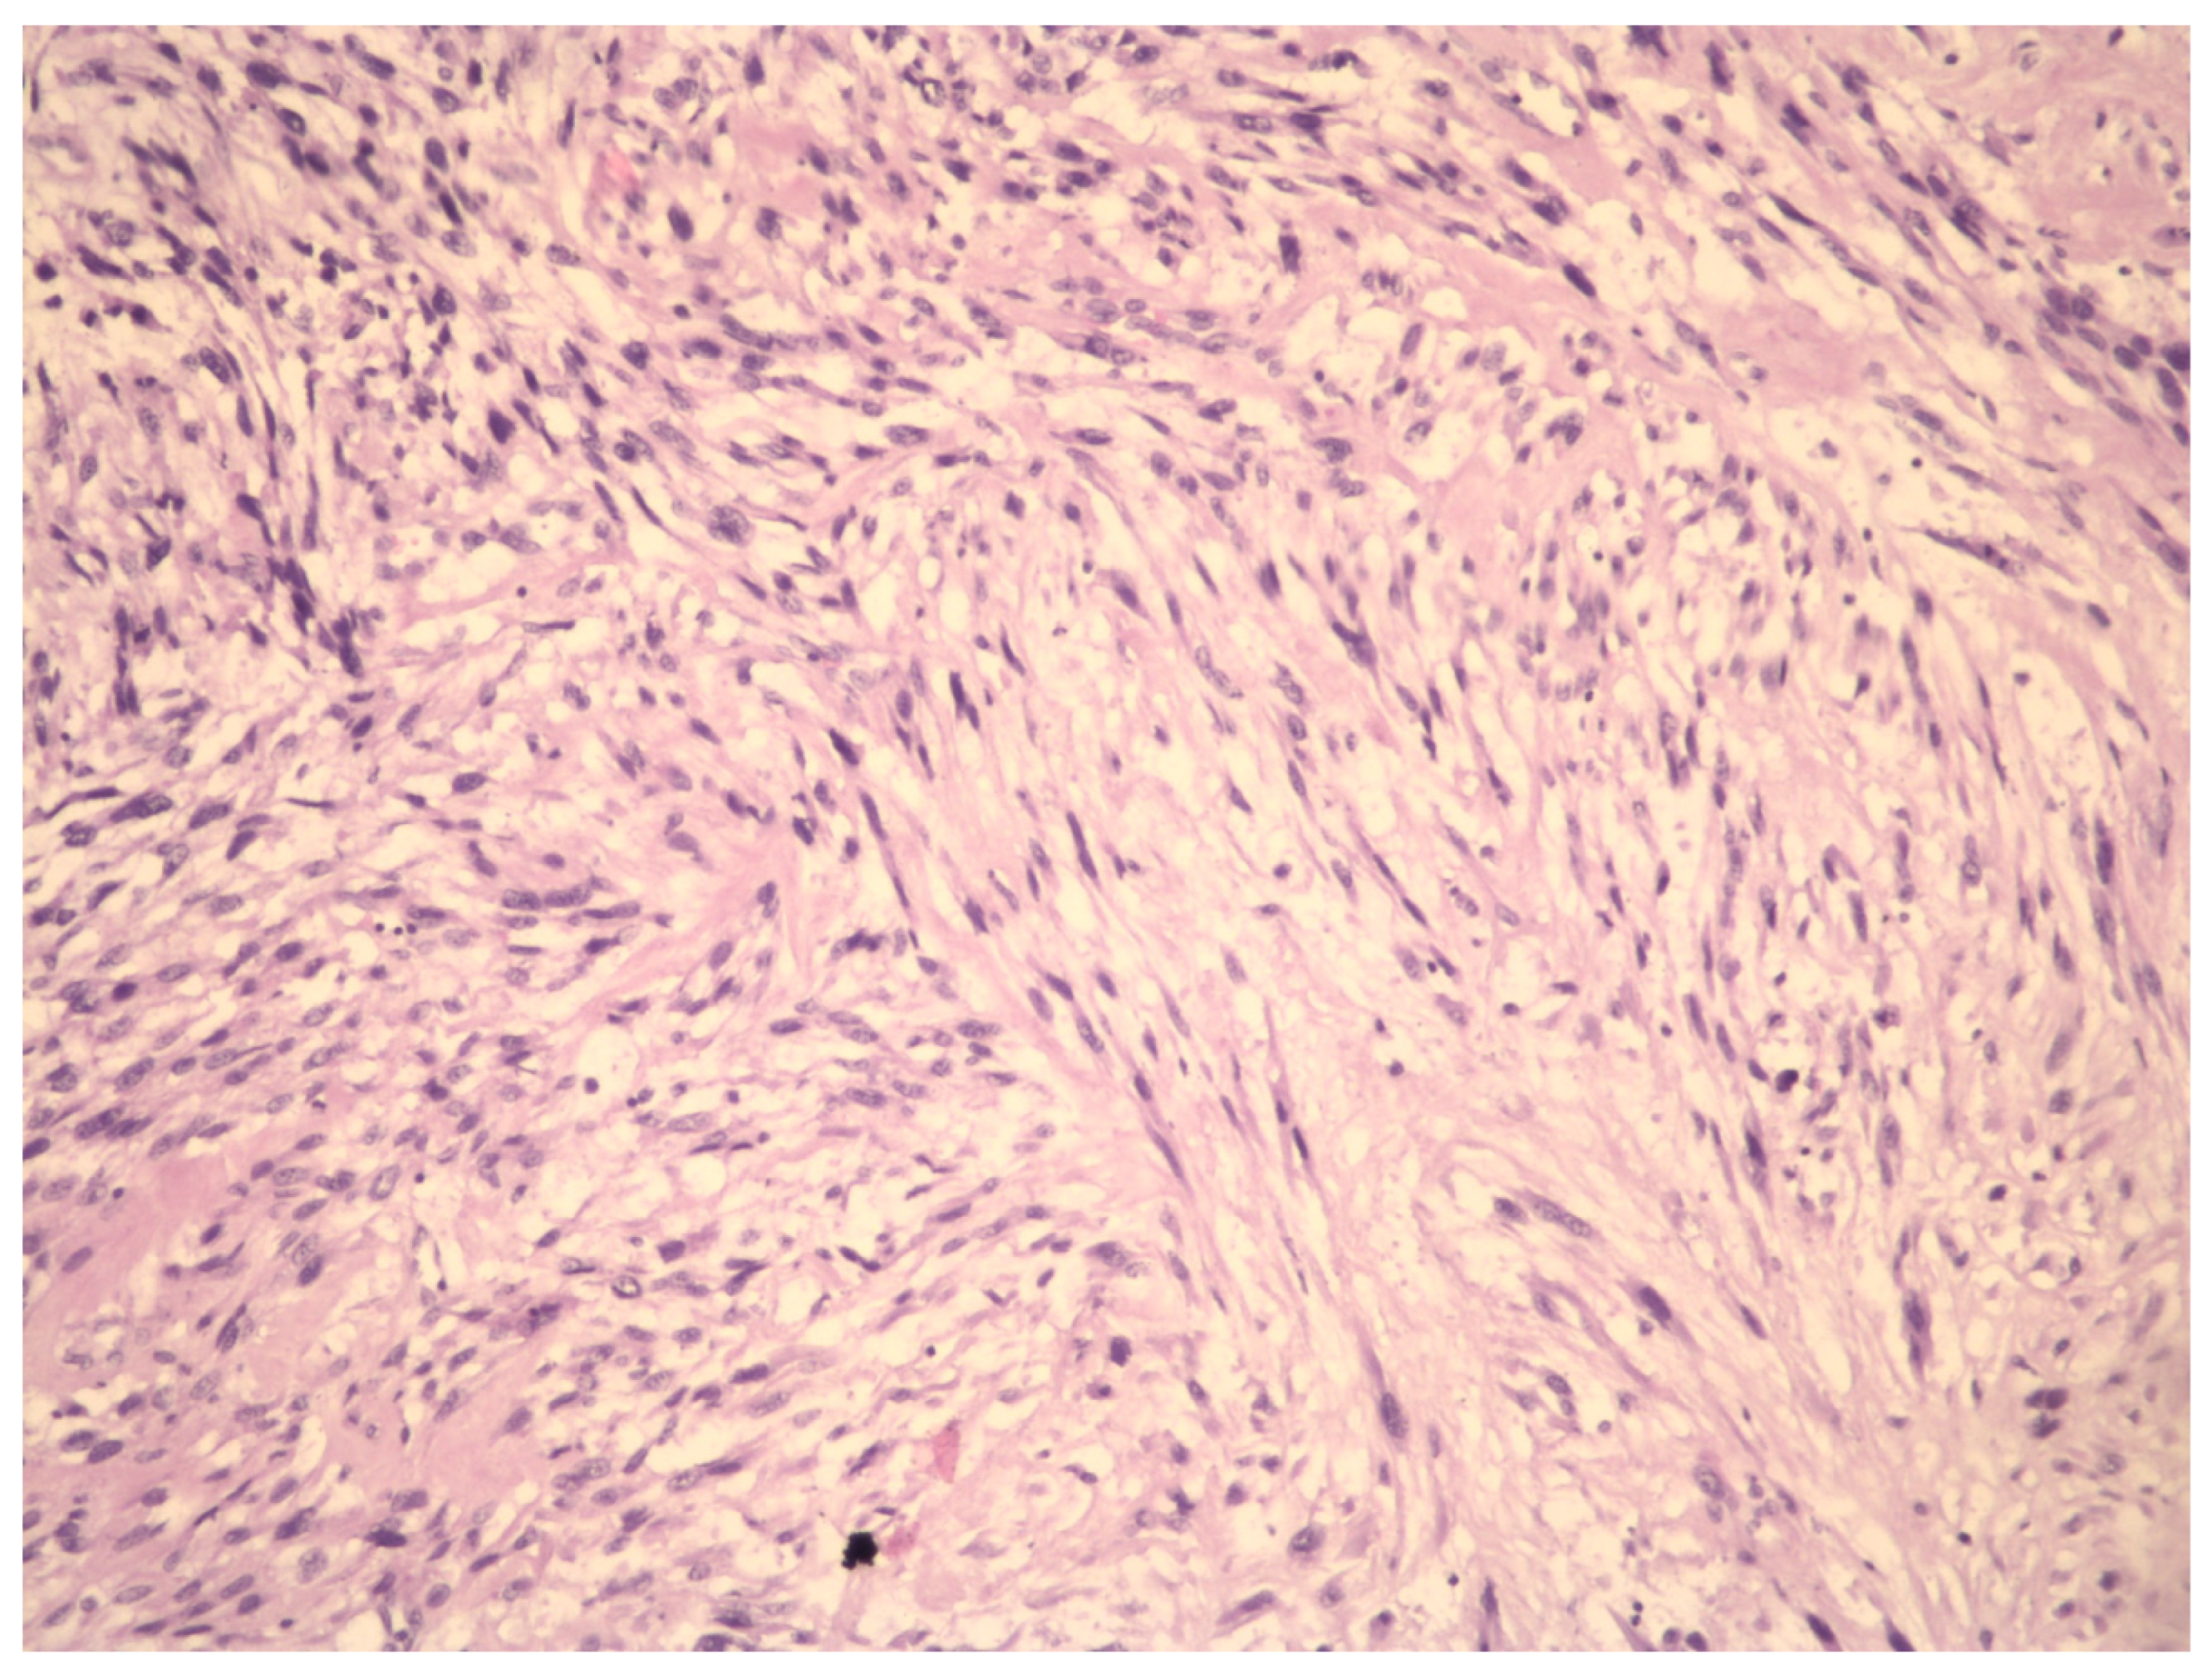

Molecular Insights in Uterine Leiomyosarcoma: A Systematic Review

3.2. Molecular Basis of Differentiation Uterine Leiomyosarcoma vs. Uterine Leiomyoma